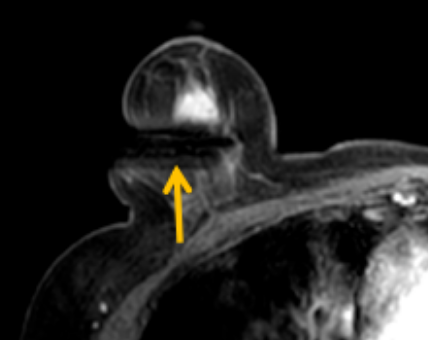

陳寶瑩評估圖像后發(fā)現(xiàn)病變?yōu)閮H僅在磁共振增強時顯示,為非腫塊樣病變,比較散,必須取得足夠多的組織才能確保病理檢查的準確性,常用的核芯針活檢獲取的組織較少,因此最終確定了磁共振引導下行真空輔助抽吸旋切活檢。取得患者及家屬認可后,陳寶瑩帶領團隊開始進行術前準備。

針對患者乳房小固定難度大這一問題,陳寶瑩通過巧妙體位和固定器的調整,順利固定好乳房。經(jīng)過磁共振多模態(tài)掃描,陳寶瑩找出病變活性成分相對集中區(qū)域,精準確定穿刺路徑,置入引導針、旋切針,到位后多角度旋切取出足量組織,拔除旋切針后即時行磁共振掃描,精準取得組織且術區(qū)出血很少,遂加壓包扎,整個過程非常順利,旋切活檢后患者回家休息。兩天后隨訪,李女士沒有任何不適,五天后皮膚上幾毫米的小切口已經(jīng)愈合。最終病理結果證實為乳腺導管原位癌,為早期乳腺癌,為患者后續(xù)針對性治療奠定了基礎。